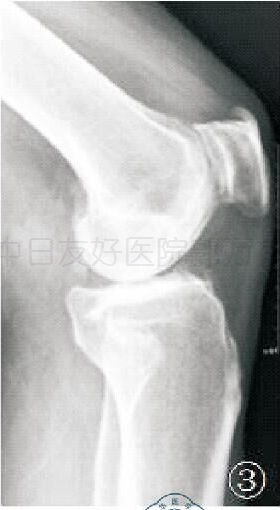

X线片二:术前侧位

侧位 X 线对于判断前交叉韧带功能完整性方面非常有价值,如果胫骨平台磨损最低点在胫骨平台的前部或中央部,磨损部位没有延伸至胫骨平台后缘,说明前交叉韧带完整,可行单髁手术;如果磨损部位延伸至胫骨平台后部,或者股骨向后半脱位,说明前交叉韧带缺失或功能严重损害,不符合单髁手术适应证。